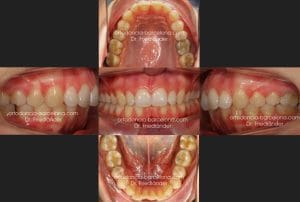

14 meses más tarde el tratamiento ya estaba terminado, se puede observar que conseguimos todos los objetivos propuestos; mejorar la salud de las encías, conseguir clase I en ambos lados y mejorar la mordida profunda.

Una de las cosas más difíciles de conseguir es el paralelismo entre las raíces de los incisivos inferiores, en la radiografía siguiente se puede comprobar que las raíces esta perfectamente paralelas entre si al final del tratamiento.

En las siguientes fotografías se puede observar como ha mejorado la salud de las encías. Las raíces de los dientes inferiores ya no esta tan salidas fuera del hueso.